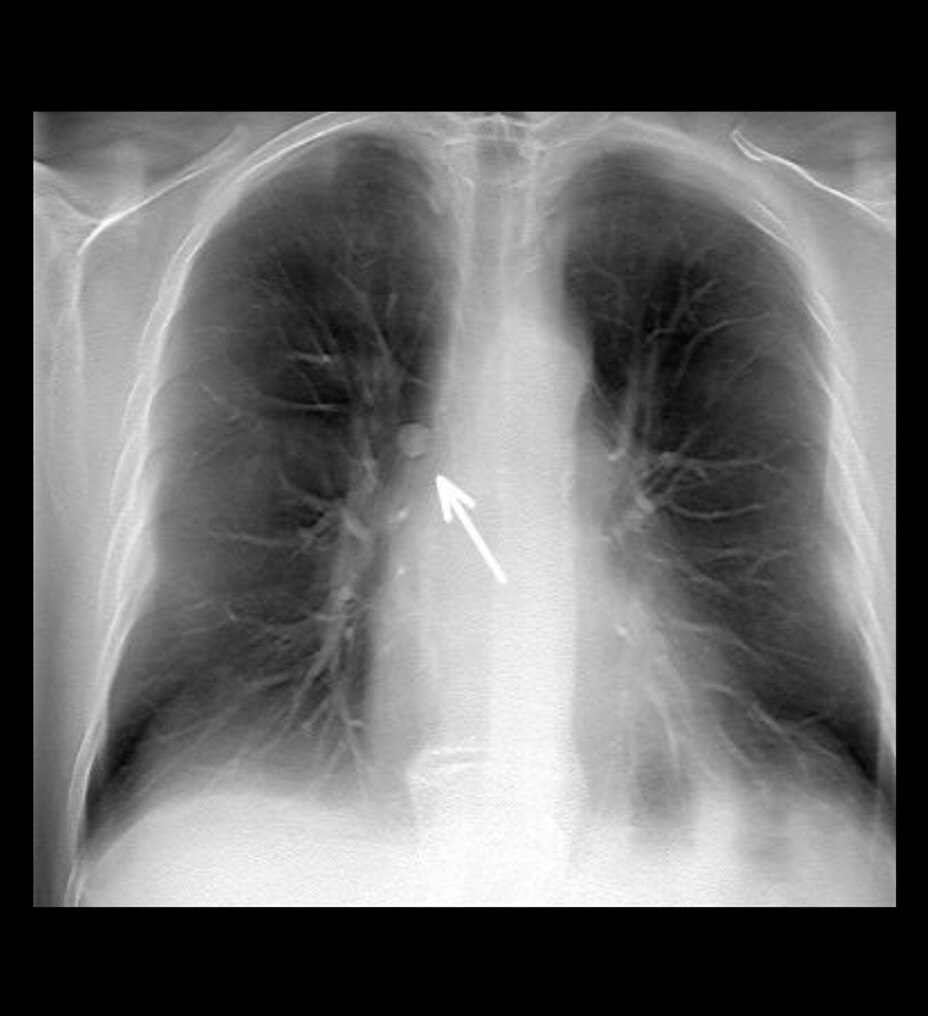

FERRAMENTA eFAST

Uma abordagem estruturada a avaliações de trauma

A ferramenta eFAST ajuda você a avaliar rapidamente o estado do paciente, de hemorragia interna a pneumotórax, e ajuda a obter consistência de usuário para usuário fornecendo uma forma de referenciar múltiplos exames ao longo do tempo.

• • Faça o escaneamento de diferentes regiões de forma sequencial, em uma ordem predeterminada ou em qualquer ordem que você desejar.

• • Documente achados com rótulos únicos e controle de tela sensível ao toque.

• • Armazene imagens em uma região corporal específica utilizando um diagrama anatômico visual com recomendações de próxima etapa fornecidas.

• • Rotule cada região com o achado relevante durante o escaneamento.

• • Visualize uma tela de revisão que sintetiza tudo durante ou após o exame, mostrando as imagens armazenadas sobrepostas sobre o diagrama anatômico.